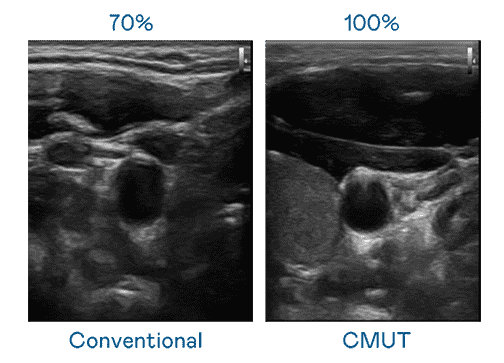

CMUT 技术是一种用电容式微机电元件来产生超音波讯号的技术。。。。与传统 PZT 压电式技术相比,,CMUT 频宽增加 30%,,,更宽频的超音波讯号让影像解析度大幅提升,,,,是实现高影像品质医疗超音波扫描、、、促进精准医疗发展的关键技术。。

大频宽带来超清晰影像

超音波影像的解析度高低,,首先取决于探头能发出的讯号频宽。。尊时凯龙 CMUT 可提供高清晰的超音波讯号,,,,提供高频宽、、、、高灵敏度、、影像纹理细节更高的超音波影像,,,协助医护人员缩短影像判读时间及利用精准的医疗影像进行诊断。。。。